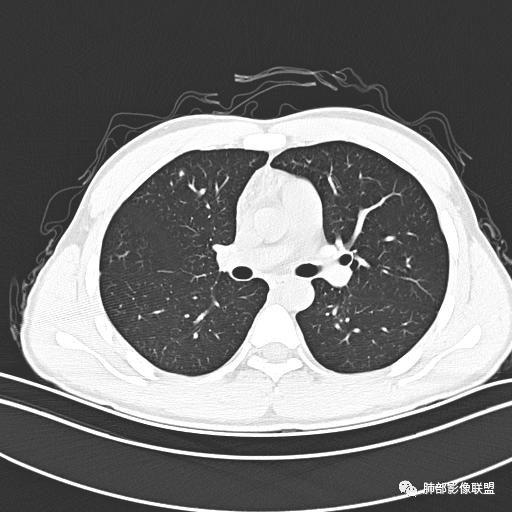

【每日晨读】年轻男性,发热+皮疹+肺内点晕

主  诉:发热、全身皮疹2天。

现病史:患者源于2天前受凉后出现发热,最高体温为38.5℃,且颜面部出现少量皮疹,无鼻塞、流涕、咳嗽、咳痰,未在意而未作特殊处理,次日全身皮疹逐渐增多至全身,伴轻度瘙痒,在当地卫生所给予抗病毒、抗感染治疗(具体用药不详)体温有所下降,但皮疹无明显消退,无腹痛、头痛,食欲无明显减退,为进一步诊治,遂于今日急来我院求治,患者目前精神尚可,体力正常,食欲正常,睡眠正常,体重无明显变化,大便正常,排尿正常。

小强:青年,发热,皮疹;双肺散在结节,周围磨玻璃,点晕征,疱疹病毒感染,鉴别荚膜组织胞浆菌,结核。 大雄:青年,急性起病,发热伴全身皮疹2天,抗病毒治疗体温有下降。双肺随机分布大小不等类圆结节,“点晕征”。考虑水痘-疱疹病毒(VZV)血播询问接触史,查体皮疹分布以及形态基本可诊断。 王开金江津中心医院呼吸科:青年男性,起病急,病程短,以发热,皮疹为首发症状,感染指标以单核细胞升高为主,胸部ct双肺多发结界,周围有晕,点晕表现,随机分布,同意於老师意见,水痘疱疹病毒血流感染累及肺。 王秀仙:双肺多发大小不等结节,周围有晕,边缘模糊,呈点晕征表现。青年,急性起病,发热伴全身皮疹2天,抗病毒治疗体温有下降。考虑疱疹病毒。鉴别荚膜组织胞浆菌。 傅昌瑜:19岁男性,发热、全身皮疹2天,单核细胞增高,双肺多发结节,结节边缘见边界不清磨玻璃影。点晕征+发热、全身皮疹+单核细胞增高——考虑水痘-带状疱疹病毒肺炎。 一切∮随缘:年轻男性,发热,皮疹两天,实验室,CRP,PCT增高,影像:双肺多发散在磨玻璃结节,边界欠清,大小不等,呈点晕征改变,以血管束周围分布为主,局部血管束略增粗,其它无明显改变,考虑:1:病毒性肺炎(水痘疱疹病毒?不知道皮肤有无改变)2:真菌(组织胞浆菌,血管侵袭性肺曲霉)3:GPA4:寄生虫(实验室没有看到嗜酸细胞增高) 赵山河:双肺散在结节,周围有晕,边缘模糊,呈点晕征表现。青年,急性起病,发热伴全身皮疹2天,抗病毒治疗体温有下降。考虑水痘—疱疹病毒感染。洪桥爱:青年男性,发热、皮疹2天,伴瘙痒,皮疹于面部首发,之后进展至全身,虽然没有对皮疹进行描述,但是从出疹时间及皮疹进展情况,伴瘙痒,应该就是个水痘患者;CT提示双肺随机分布结节影,部分结节伴有边界不清晕征,考虑水痘血播肺。 刘强:年轻男性,急性起病,皮疹,发热,抗感染治疗体温下降,说明有效。影像表现为散在点晕征,感染类疾病谱(疱疹病毒,真菌,结核),结合年龄,皮肤皮疹,考虑水痘-疱疹病毒性肺炎。 小兜:男性,19岁,发热皮疹两天,颜面部至全身,CRP,降钙素及单核增高。CT示双肺散在小结节,周围伴磨玻璃影,点晕征,考虑为水痘-带状疱疹病毒(varicella-zoster virus,VZV)肺炎 必有路:青年,皮疹+发热+“点晕征”→水痘-疱疹病毒(VZV) 许慧良:青年男性患者,发热、皮疹2天,体温最高38.5℃,第3天皮疹扩展至全身,伴瘙痒,胸部CT:双肺多发随机分布的小结节,结节周边见边界模糊的晕征,考虑水痘病毒感染流心明智:男,19,急性起病,发热伴全身皮疹2天。出疹顺序头→全身,抗病毒有效。胸部CT:两肺多发大小不等类圆形实性小结节影,随机分布,结节周围环绕GGO,边界模糊,呈点晕征。出疹特点是关键,未提示。考虑:血播病毒性肺炎,水痘-疱疹病毒?麻疹?鉴别荚膜组织胞浆菌、TB、血管炎、寄生虫等。 浪迹天涯:病灶多为5-10mm大小结节,结节周围可见磨玻璃样的晕环,常多发,可分布于肺内任何区域,考虑水痘—带状疱疹病肺炎如果短时间内有新的一个区域浸润,更加能说明,